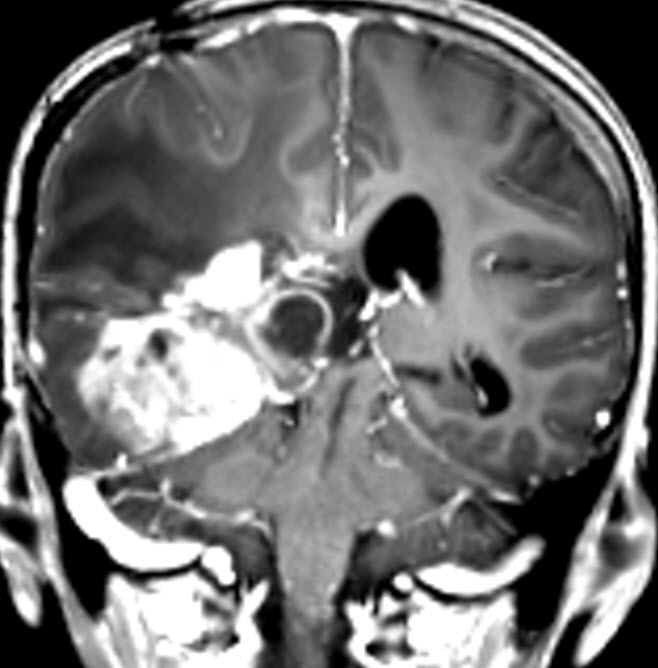

Coronal MRI done the next postoperative day. Notice how near the dissection to the right internal capsule.